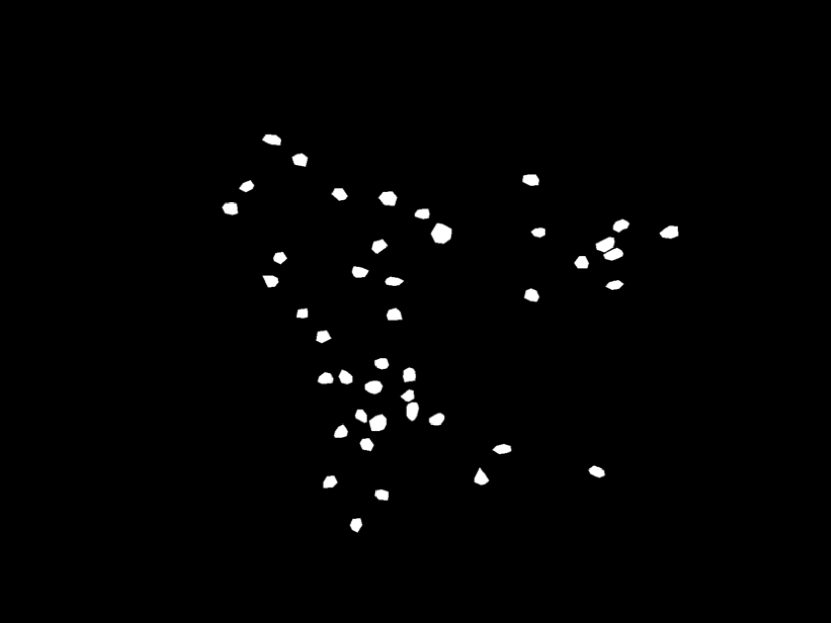

(f) Yellow mask example

Figure 2: Data preview. The figures show examples of fluorescence micrscopy pictures (Figures 2(a), 2(b) and 2(c)) and the corresponding ground-truth binary masks (Figures 2(d), 2(e) and 2(f)).

The FNC collection provides annotations of multiple types, encoded in several standard formats. In the masks folder, we find the binary masks typically used for segmentation tasks (cf. Figures 2(d), 2(e) and 2(f)). The correspondence between the masks and the respective images can be established based on the filenames. The other folders store a light-weight encoding of the binary masks, enriched with additional annotation types/formats.

Table 1 reports summary statistics for the distribution of key features at the image and object levels, that can be leveraged for technical validation. For instance, the annotated objects display an average area of nearly 75, 247, and 133 μm2𝜇superscript𝑚2\mu m^{2} for green, red, and yellow cells, respectively. These values align with the expected size of the biological structures represented in each image collection. Additionally, the analysis of Feret and equivalent diameters provides an understanding of the typical form of the stained objects. In particular, the Feret diameter[25] can be interpreted as a measure of the maximum extension of an object, whereas the equivalent diameter represents the diameter the object would have if it were a perfect circle with the same area. Thus, comparing these two metrics can offer insight into the objects’ shape regularity. For green cells, the values for the two measurements are relatively close (roughly 12 VS 10 μm𝜇𝑚\mu m), suggesting that these cells are broadly circular or oval in shape. A similar conclusion can be drawn for the yellow stains, albeit with slightly more variability (approximately 17 and 13 μm𝜇𝑚\mu m), indicating generally regular shapes with occasional deviations. In the case of red objects, instead, the comparison is markedly different. This time we observe a Feret diameter around 26 μm𝜇𝑚\mu m against an equivalent diameter of 17, which suggests that these stains are typically elongated in one direction rather than concentrated around a center of mass. All these observations are also corroborated when visually inspecting annotated cells, which confirms prior expectations about objects size and shapes based on the nature of the marked structures.

Moreover, the substructures of interest have a fluid nature. Also, the shot can capture different two-dimensional sections depending on how the cells are oriented within the tissues. As a consequence, the size and the shape of the stained cells can vary significantly (cf. objects dimension in Figures 2(d), 2(e) and 2(f)), further complicating the discrimination between cells and the background.